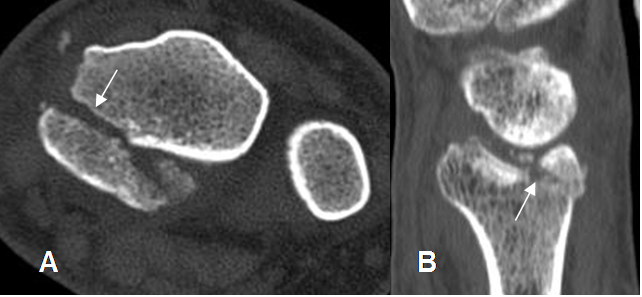

Fig 36. Fractura de Barton.

A: TAC axial y B: TAC reconstrucción sagital. Fractura intra-articular, que compromete la parte posterior del radio.